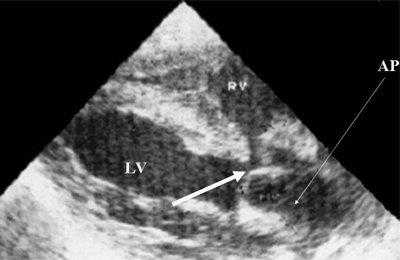

В равной степени это относится к дефекту межжелудочковой перегородки (рис. 6), простой форме транспозиции магистральных сосудов (рис. 7, 8), транспозиции магистральных сосудов с дефектом межжелудочковой перегородки (синдром Тауссиг - Бинга) (рис. 9), общему желудочку (рис. 10), общему артериальному стволу (рис. 10), двойному отхождению сосудов от одного из желудочков сердца (рис. 11).

Рис. 10. Общий желудочек с отхождением TRUNCUS ARTERIOSUS. Стрелками показано разделение TRUNCUS ARTERIOSUS на аорту и ствол легочной артерии.

LV и RV - левый и правый желудочек, АР - легочная артерия, АО - аорта, VSD - дефект межжелудочковой перегородки.